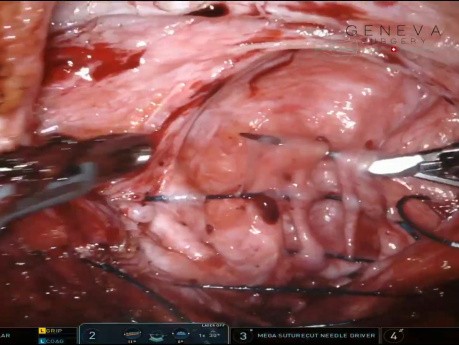

Reparación laparoscópica de una hernia diafragmática...

La reparación laparoscópica de una hernia diafragmática grande y compleja del lado derecho se presentó en la sesión SS02: Foregut Session 1 por el Dr. Douglas Cassidy el 17 de abril de 2024 durante la...